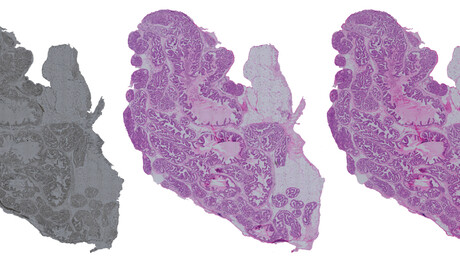

The artificial intelligence method developed in the new study produces computational images that very closely resemble those produced by the actual chemical staining process. This virtually stained image can then be used for inspecting the morphology of the tissues.

Chemical staining has been the cornerstone of studying histopathology for more than a century and is widely applied in, for example, cancer diagnostics. As explained by the University of Eastern Finland’s Leena Latonen, who led the experimental part of the study, “Chemical staining makes the morphology of the almost transparent, low-contrast tissue sections visible. Without it, analysing tissue morphology is almost impossible for human vision. [But] chemical staining is irreversible, and in most cases it prevents the use of the same sample for other experiments or measurements.”